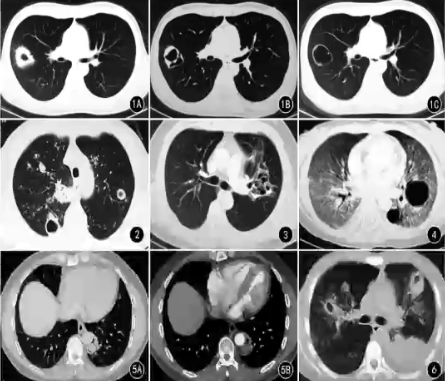

侵袭性肺真菌感染空洞CT特点

❖ 厚壁(≥3cm)空洞常见,治疗后空洞壁多最终变薄

❖ 内壁多光滑

❖ 腔内液气平少见

❖ 无特定好发部位

❖ 空洞可伴有晕征、空气新月征或气环征

❖ 空洞内结节增强无强化

❖ 除空洞外,肺部可见多发病变(斑片、结节等)